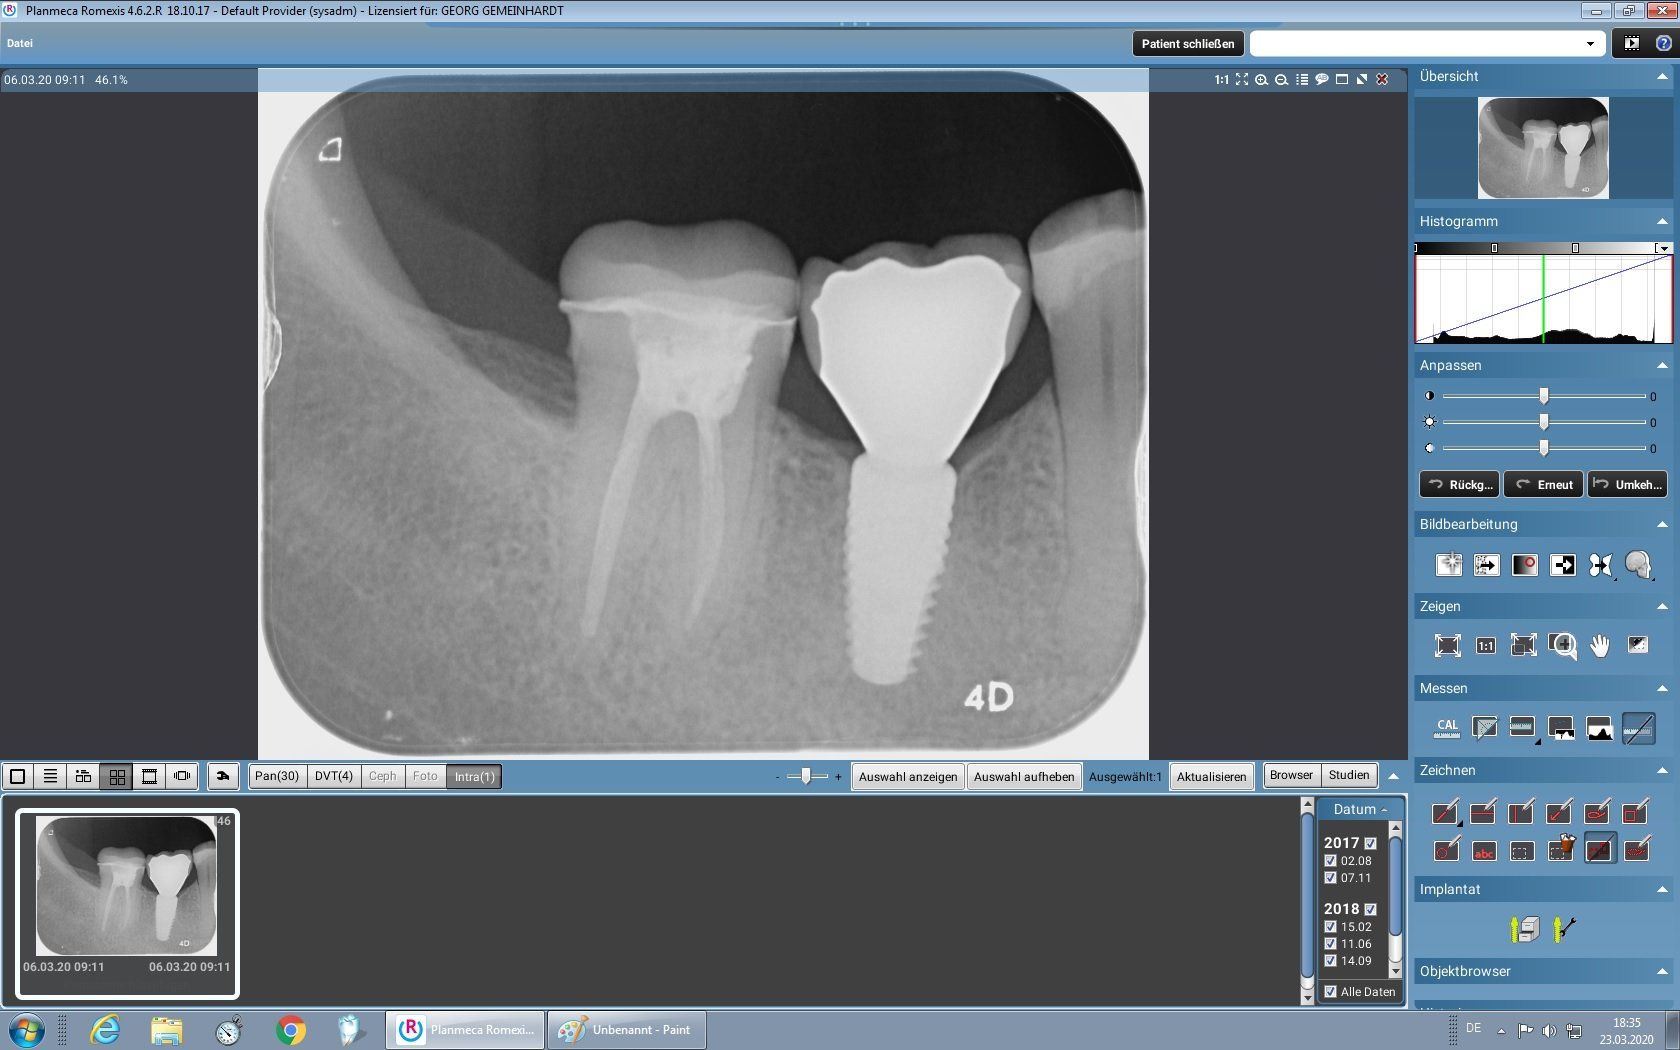

Der implantologische Zahnersatz setzt sich aus drei Komponenten zusammen:

- der künstlichen Wurzel (dem eigentlichen Implantat)

- dem Implantataufbau

- der auf dem Implantat verankerten Krone, Brücke oder Prothese